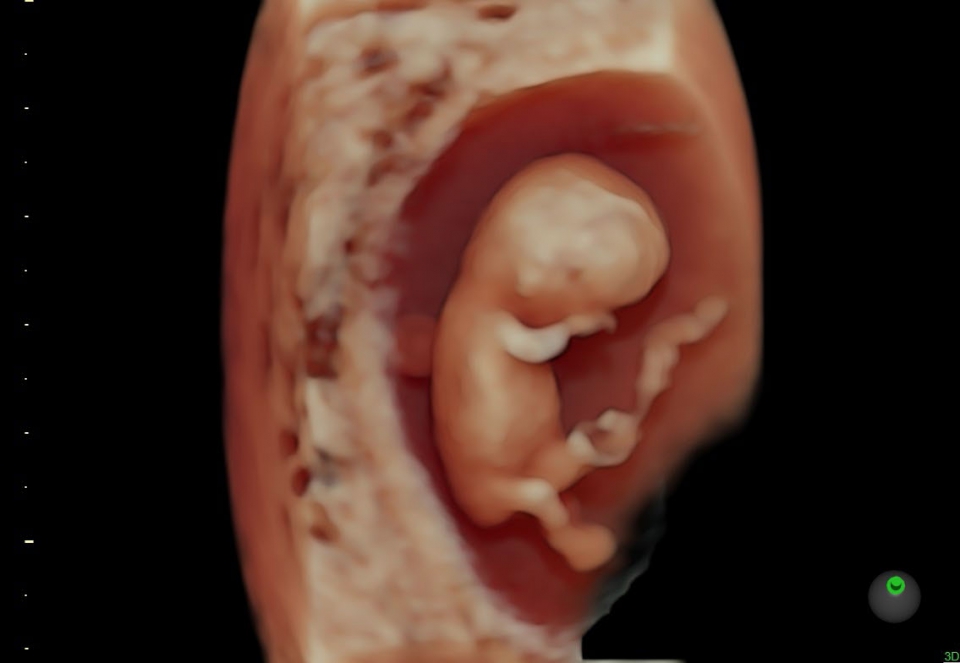

УЗИ аппарат Voluson S10 позволяет проводить обследования высочайшего уровня с максимальной точностью диагностики. Благодаря технологии Voluson Core Architecture достигнут высокий уровень качества изображений с возможностью последующей обработки и анализа даже после проведения скрининга. Технология HDlive делает изображения удивительно реалистичными и объемными.

• SonoRenderlive (Автоматическое объемное изображение): Эта функция упрощает получение объемного изображения путем автоматического выбора положения плоскости визуализации для 3D- и 4D-режимов. Это сокращает необходимость вручную настраивать параметры и упрощает процесс получения объемных изображений.

• HDlive в 3D и 4D - режим перемещаемого виртуального источника освещения - "виртуальная фетоскопия"